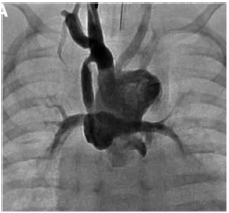

Na angiografia a seguir é possível identificar uma intervenção cirúrgica muito executada na cardiologia pediátrica.

Assinale a opção que indica a cirurgia e uma indicação adequada para ela.